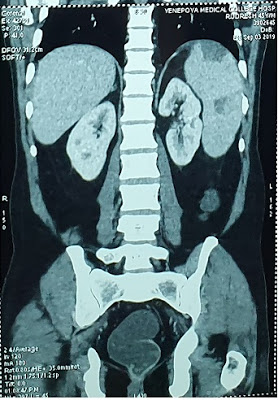

Later CECT was done which showed – hepatosplenomegaly with hypoechoic lesions in spleen s/o infarct as shown in Fig1 and Fig 2